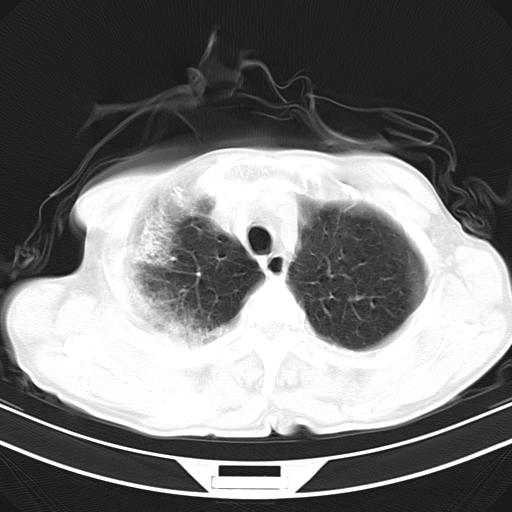

标题: CT23873:男,70,发烧咳嗽咳痰10余天,查痰结核菌阴性 [打印本页]

男,70,发烧咳嗽咳痰10余天,查痰结核菌阴性。否认以前有肺病史。治疗10天后症状减轻。 img]/upload/forum/2009/12/302117469692.jpg[/img]

影像所见:右上肺见一巨大厚壁空洞,内壁欠光整,右上肺广泛斑片状、大片状模糊阴影。

抗炎治疗10天后复查:右上肺模糊阴影明显减少。

诊断意见:考虑右上肺巨大含气囊肿并感染,建议继续治疗后复查。

不支持点:空腔壁较厚,欠光滑。询问病人是否有反复感染病史?

结核临床及影像,结核暂不考虑。